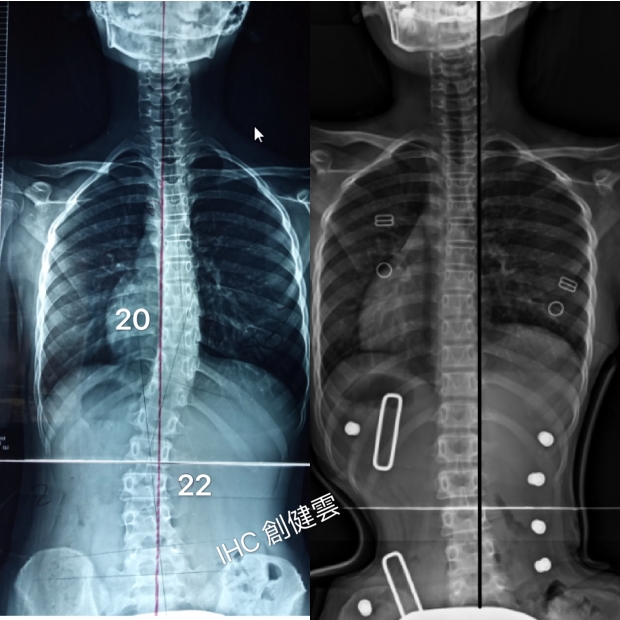

18歲脊椎側彎女孩

胸彎28度,腰彎45度